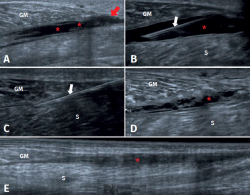

The most frequent ultrasound finding in triceps surae muscle injuries is a hypoechogenic zone at the distal myotendinous junction of the medial gastrocnemius muscle(29). The latter appears as a serohematic content between the muscle fibres and the myofascial plane, associated to an increase in echogenicity of the adjacent musculature as a manifestation of oedema and hyperaemia in the colour Doppler study(9), as can be seen in Figure 1. Delgado et al., in 141 patients clinically diagnosed with tennis leg, found that 67% of the patients presented partial rupture of the medial gastrocnemius, 1.4% presented associated plantaris tendon rupture, and 21% presented an intermuscular fluid collection between the medial gastrocnemius and the soleus muscle - thus affording an improved perspective of the possible differential diagnosis(30). On the other hand, involvement of the lateral gastrocnemius is much less common (up to 14% of the cases)(31). Ultrasound also plays a role in the lesions follow-up. In a normal evolutive scenario, we can observe gradual reduction of the oedema, resolution of the fibrillar defect and reabsorption of the fluid collections(32). It is also common to observe signs of organization of the haematoma between the gastrocnemius and the soleus, evolving as a fusiform fibrous scar without inflammatory elements, as can be seen in Figure 2.

Figure 2. Evolution of a medial gastrocnemius fibrillar tear. A: ultrasound view of an acute tear of the distal myotendinous junction of the medial gastrocnemius (MG) (red arrow), associated to haematoma in the aponeurotic plane adjacent to the soleus (S) (asterisks); B: needle positioning before aspiration (white arrows) of the haematoma under ultrasound guidance; C: needle aspiration (white arrows) of the haematoma under ultrasound guidance, extraction of 70 cc; D: control after 10 days, haematoma relapse, of smaller size, with septa and signs of organization; E: control after 31 days, showing organization of the haematoma, evolving towards a fibrous scar cord, without signs of inflammation. Complete healing of the tear (red arrow).

In the subacute phase (7-10 days), fluid collections can be aspirated under ultrasound guidance to improve the rehabilitation process(32). Succinctly, aspiration preferably should be made in the subacute phase, and proves more effective if fluid is obtained (versus pure haematoma) and total drainage of the serohaematic collection is achieved(40). Special care to avoid iatrogenic neurovascular problems is required(40). On the other hand, it is essential to restrict the technique in the presence of active bleeding, coagulopathy or a lack of skill in handling the needle and ultrasound system(40). Figure 2 details the course of a medial gastrocnemius fibrillar tear and total drainage of the fluid collection in a patient prior to rehabilitation.